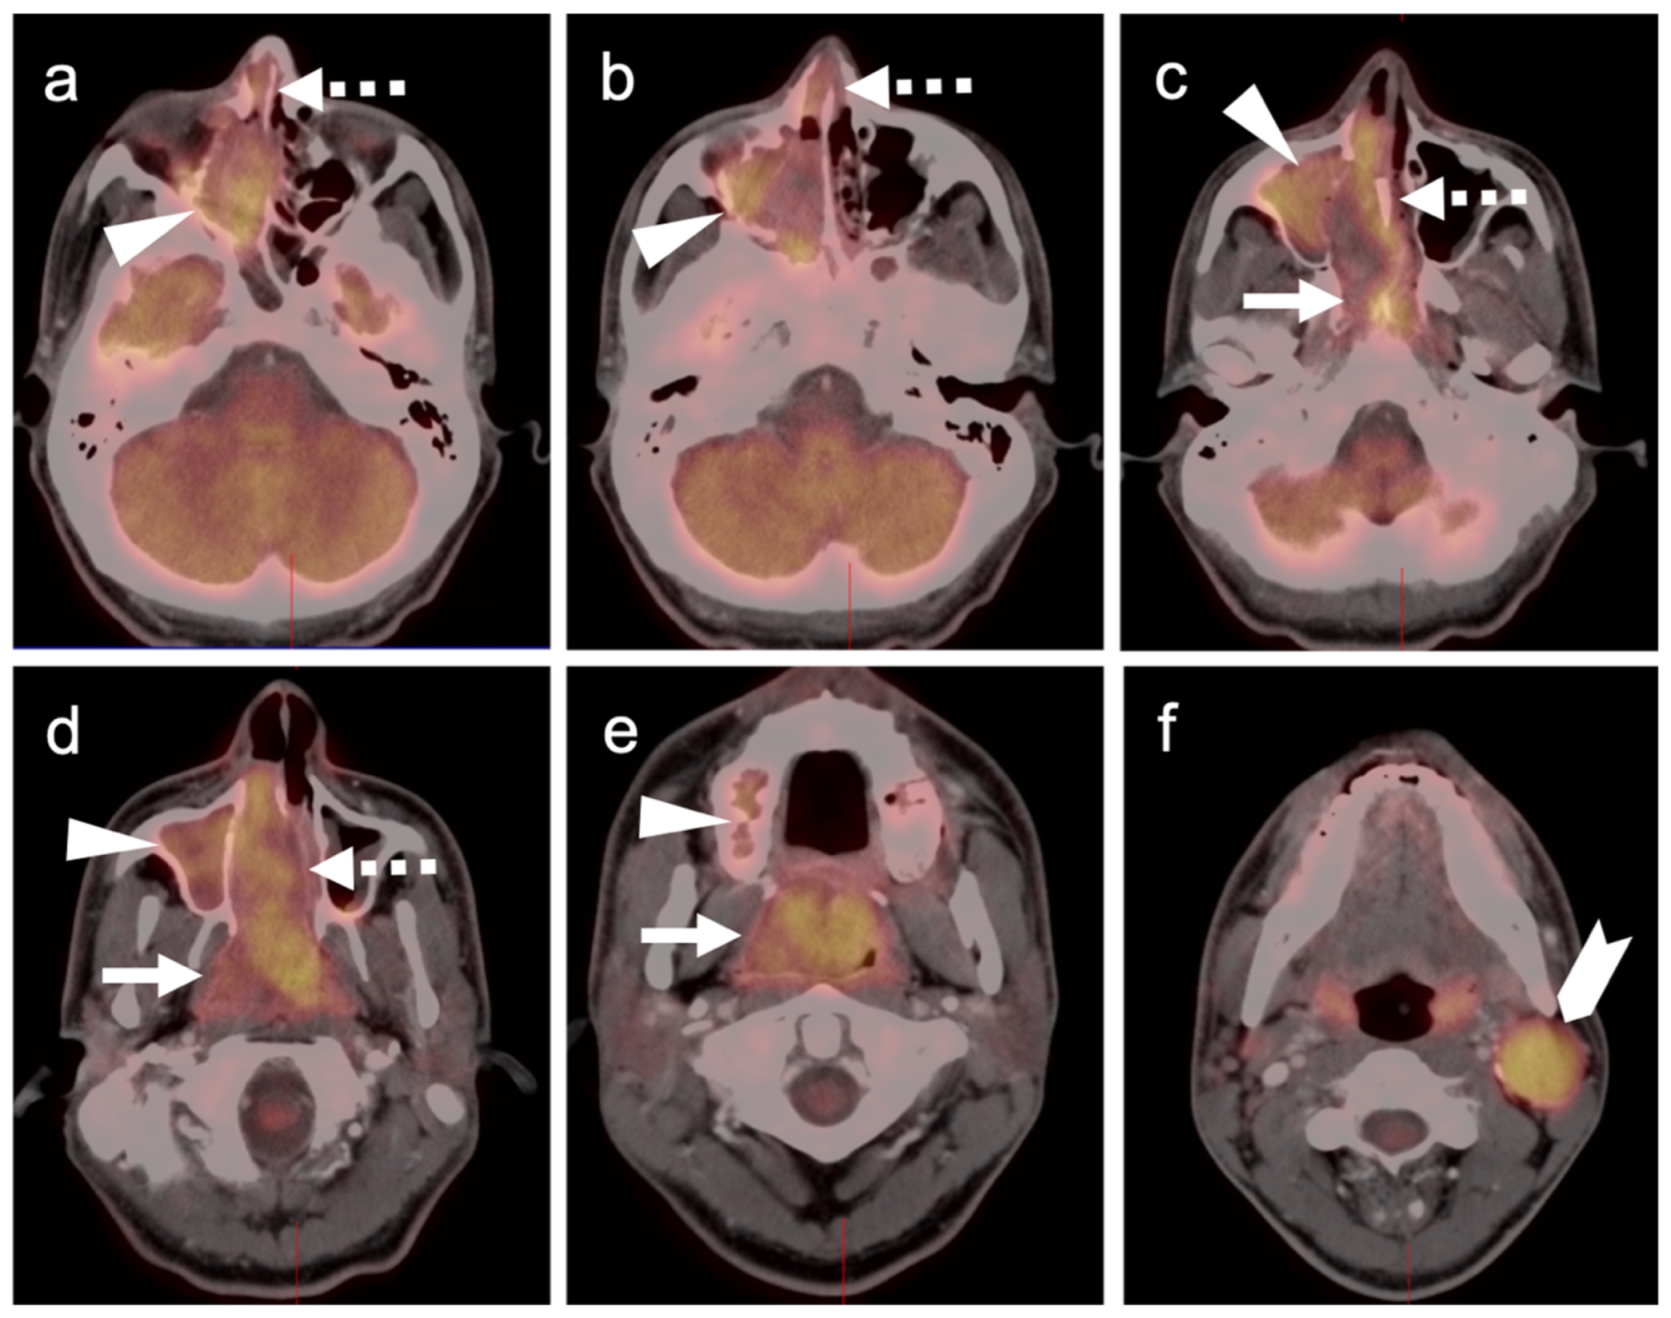

2.3.3. Mucosal Melanoma

- Goerres, G.W.; Stoeckli, S.J.; Von Schulthess, G.K.; Steinert, H.C. FDG PET for Mucosal Malignant Melanoma of the Head and Neck. Laryngoscope 2002, 112, 381–385. [Google Scholar] [CrossRef]

- Murphy, G.; Hussey, D.; Metser, U. Non-cutaneous melanoma: Is there a role for18F-FDG PET-CT? Br. J. Radiol. 2014, 87, 20140324. [Google Scholar] [CrossRef] [Green Version]